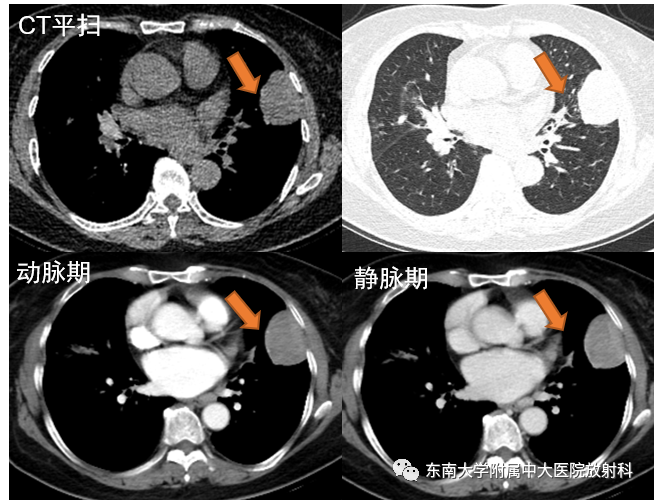

病例3

女,75岁

主诉:发热10余天

现病史:患者10余天前接触流感病人后出现发热,体温最高38.6℃,伴咳嗽咳痰,夜间为甚,痰为黄色,伴全身乏力,活动后出现气喘